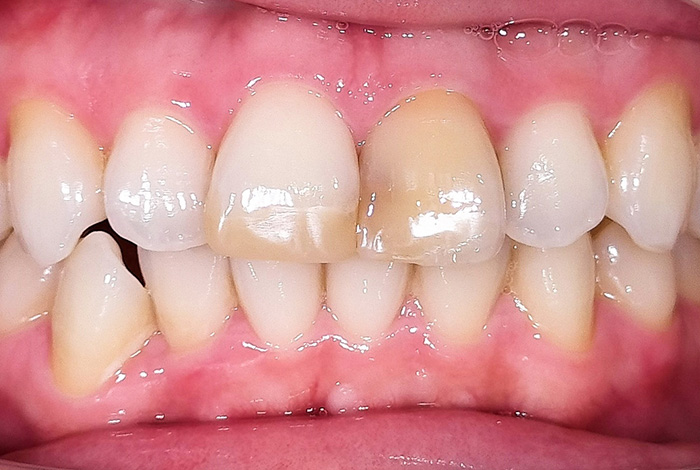

前歯の見た目と噛み合わせのバランスを整えたケース

「前歯が強くかみ込んでいる気がする」「歯並びだけでなく、噛み合わせも気になる」

今回の患者様は、ディープバイト(過蓋咬合)による前歯の見た目と噛み合わせを気にされて来院されました。ディープバイトとは、上の前歯が下の前歯に深く重なっている噛み合わせのことで、見た目の問題だけでなく、前歯や顎への負担につながることがあります。

本症例では、マウスピース型矯正装置(インビザライン)を用いて治療を行いました。合計84枚のアライナーを使用し、歯並びだけでなく咬合の深さにも配慮しながら治療を進めました。

治療後は、前歯の見た目のバランスが整い、噛み合わせも改善しました。